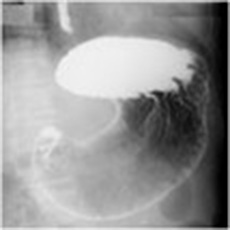

透視撮影装置

人体を透過したX線をモニターでリアルタイムに見ることができます。造影剤(バリウムなど)を使用する胃、腸の検査のほか、骨折の整復、内視鏡を用いての胆管結石の除去、腸閉塞の時にお腹にチューブを入れる検査等に使用しています。また、2階X線テレビ室では健康診断のバリウムの検査を行っております。